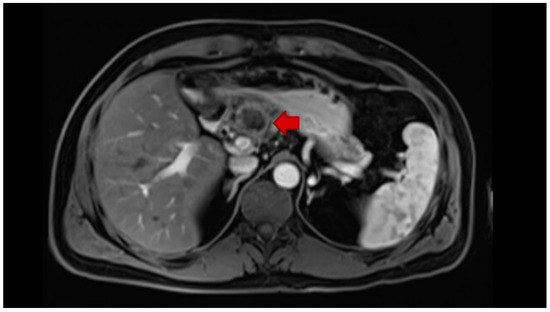

- Fábrega-Foster, K.; Ghasabeh, M.A.; Pawlik, T.M.; Kamel, I.R. Multimodality imaging of intrahepatic cholangiocarcinoma. HepatoBiliary Surg. Nutr. 2017, 6, 67–78. [Google Scholar] [CrossRef] [PubMed]

- Seo, N.; Kim, D.Y.; Choi, J.Y. Cross-sectional imaging of intrahepatic cholangiocarcinoma: Development, growth, spread, and prognosis. Am. J. Roentgenol. 2017, 209, W64–W75. [Google Scholar] [CrossRef]

- Kim, R.; Lee, J.M.; Shin, C.I.; Lee, E.S.; Yoon, J.H.; Joo, I.; Kim, S.H.; Hwang, I.; Han, J.K.; Choi, B.I. Differentiation of intrahepatic mass-forming cholangiocarcinoma from hepatocellular carcinoma on gadoxetic acid-enhanced liver MR imaging. Eur. Radiol. 2016, 26, 1808–1817. [Google Scholar] [CrossRef]